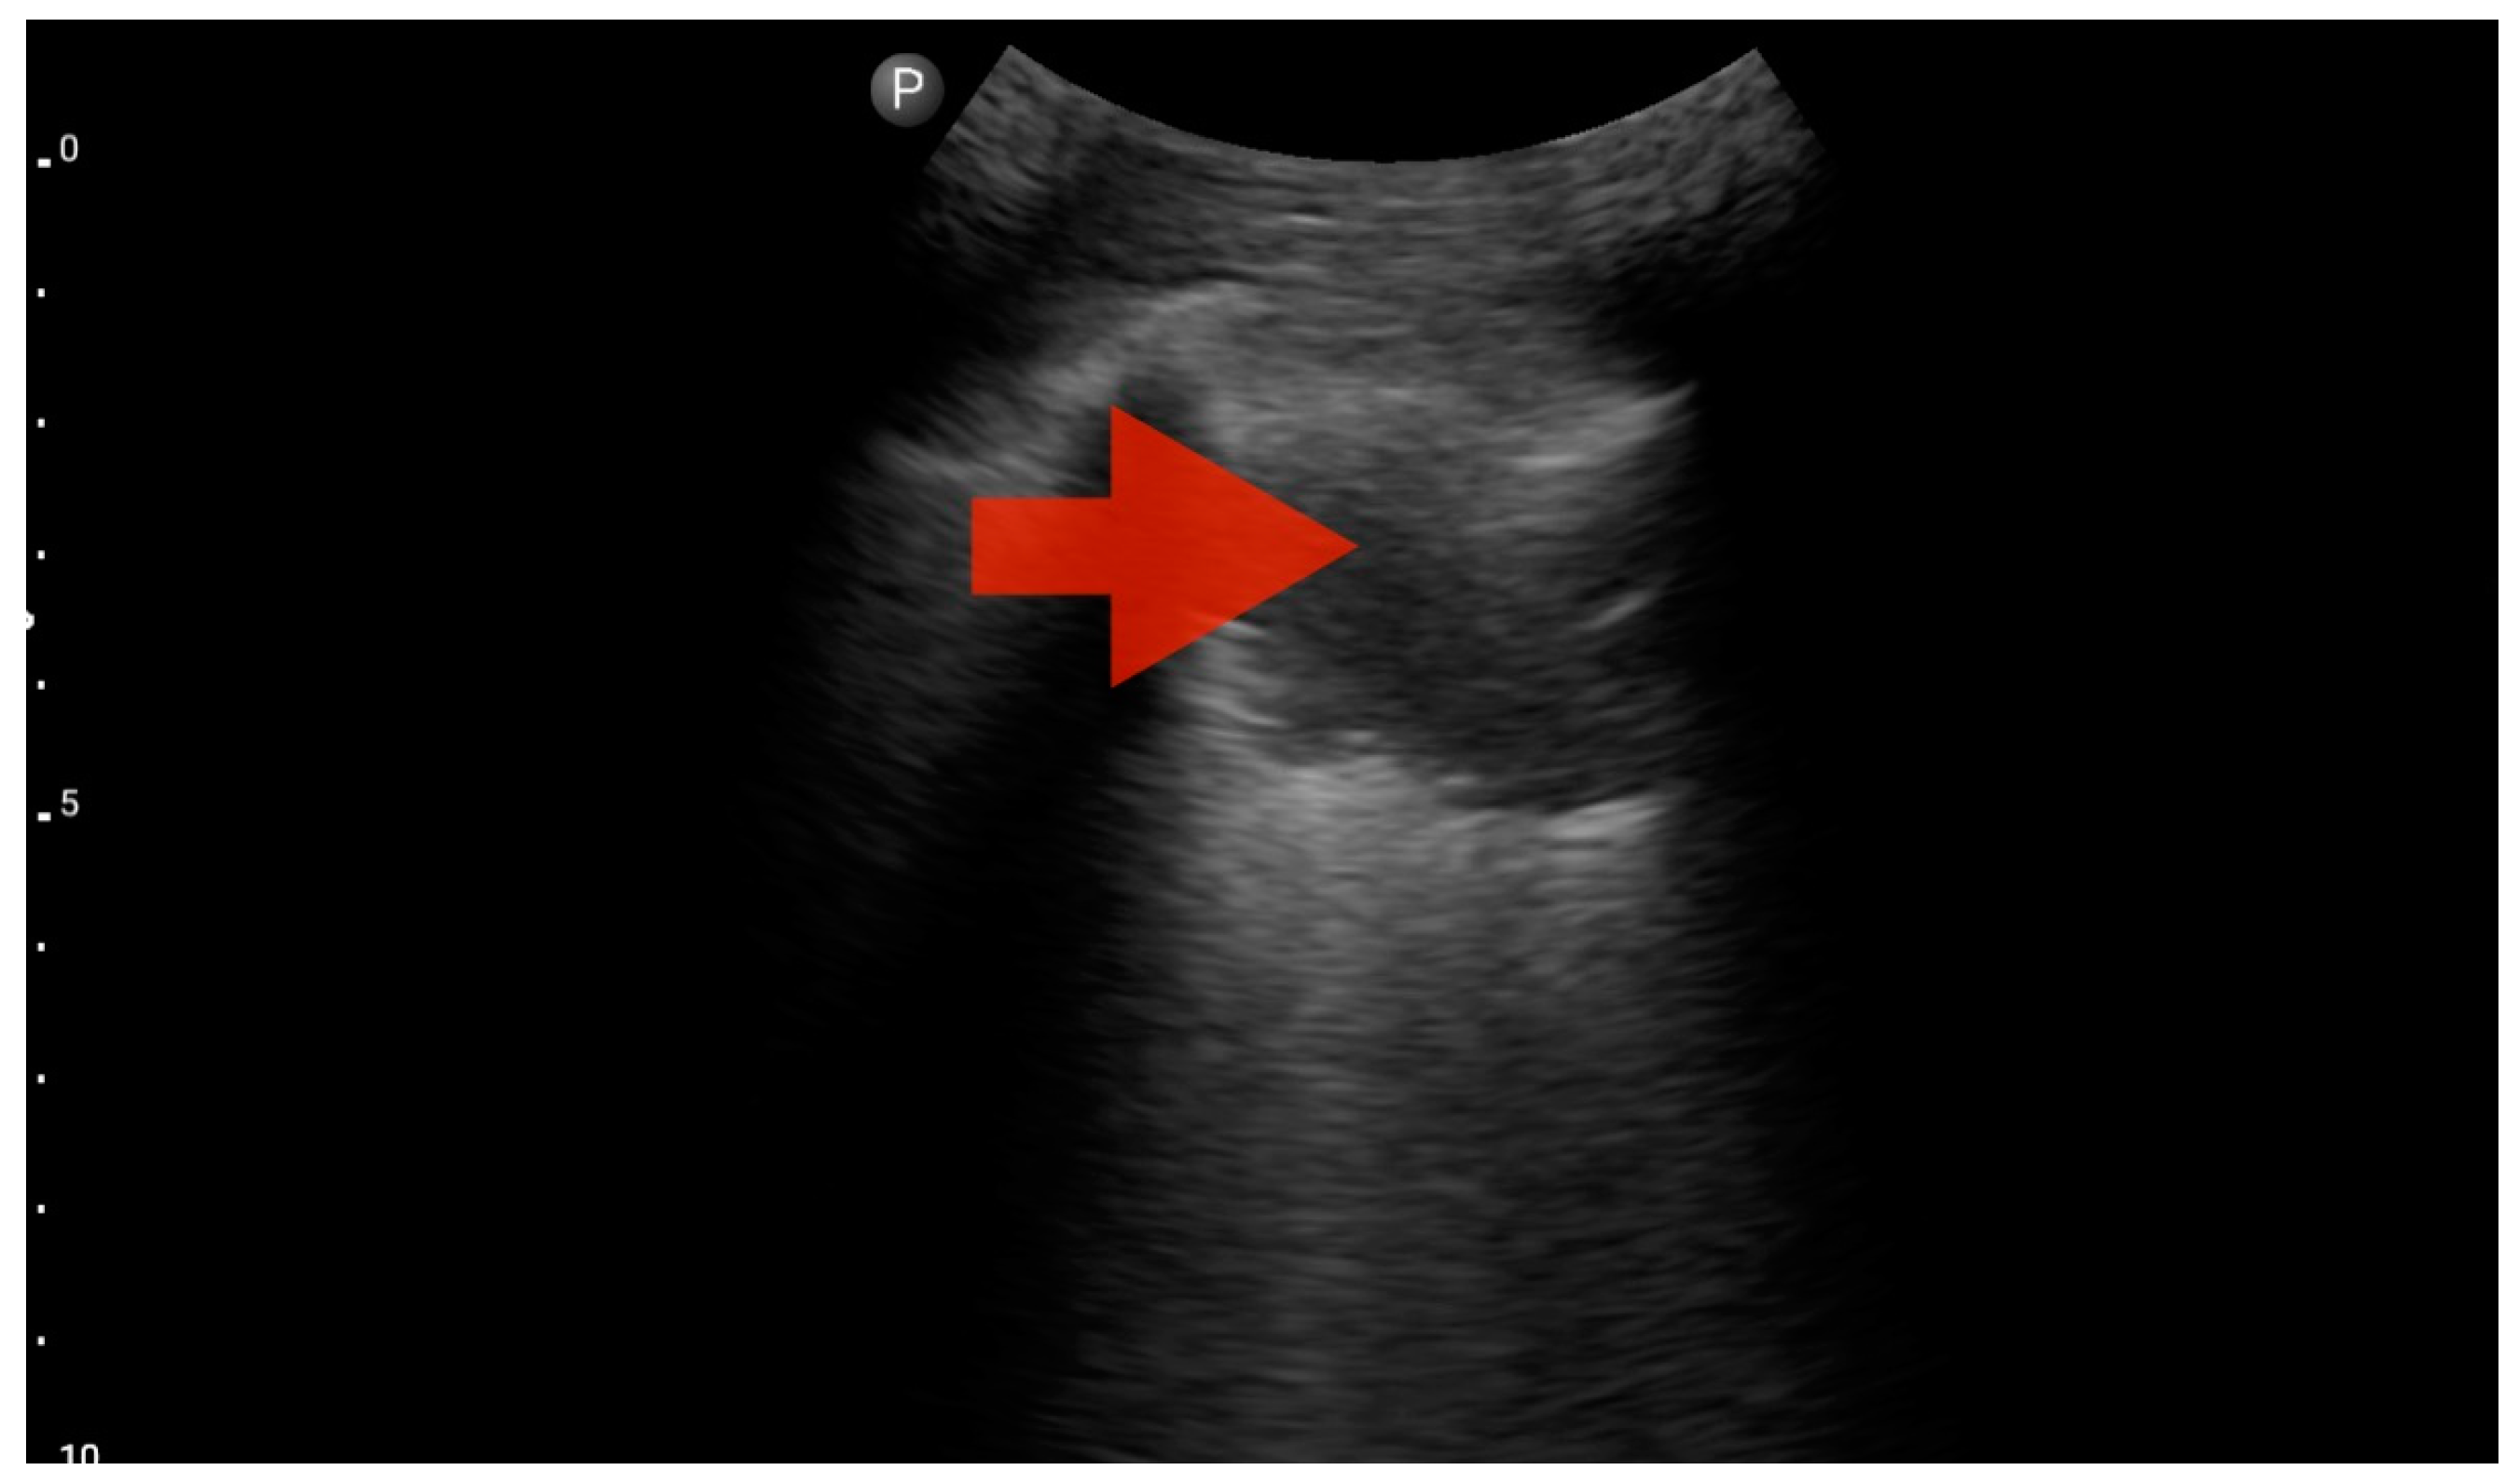

Figure 8.

Profile B (BLUE protocol). Convex probe, top of the lung (2nd–3rd intercostal space), the red arrow indicates the vertical artifact of the B line (source: author’s material—DK).